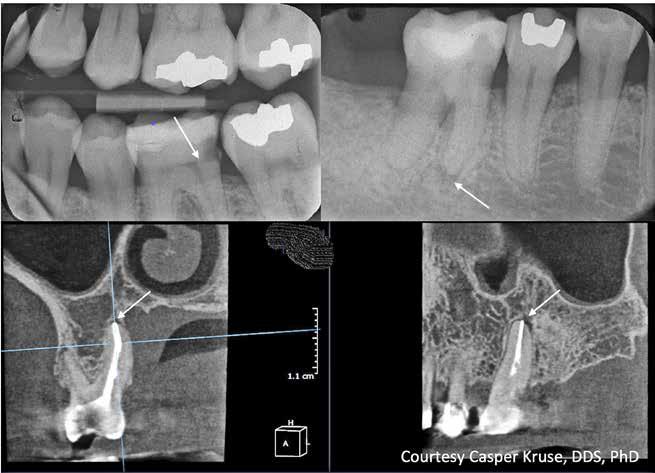

B.

der viser en lille, men tydelig radiolucens (pil) I relation til den ikke-rodfyldte 6-. Hvis der kan ses en radiolucens, er der sandsynligvis apikal parodontitis til stede. Det intraorale radiologiske billede underestimerer ofte læsionens omfang (Bender, 1982)

C. CBCT (sagittalt og koronalt aspekt), der viser en rodfyldt +6 med lille apikal radiolucens (pile). Ved rodfyldte tænder overestimerer CBCT ofte forekomsten af apikal parodontitis, og fundene skal derfor vurderes kritisk. (Kruse et al., 2019).

Fig. 2. A. Bite-wing radiograph showing deep caries in tooth 36, but with dentin visible between lesion and pulp (arrow). In such cases, the pulpal inflammation is usually reversible, and treatment should aim to preserve pulp vitality (Bjørndal et al., 2010).

B. Intraoral periapical image showing a small but clear radiolucency (arrow) associated with the non-root-filled tooth 46. If a radiolucency is visible, apical periodontitis is likely present. The intraoral radiographic appearance often underestimates the extension of the lesion (Bender, 1982)